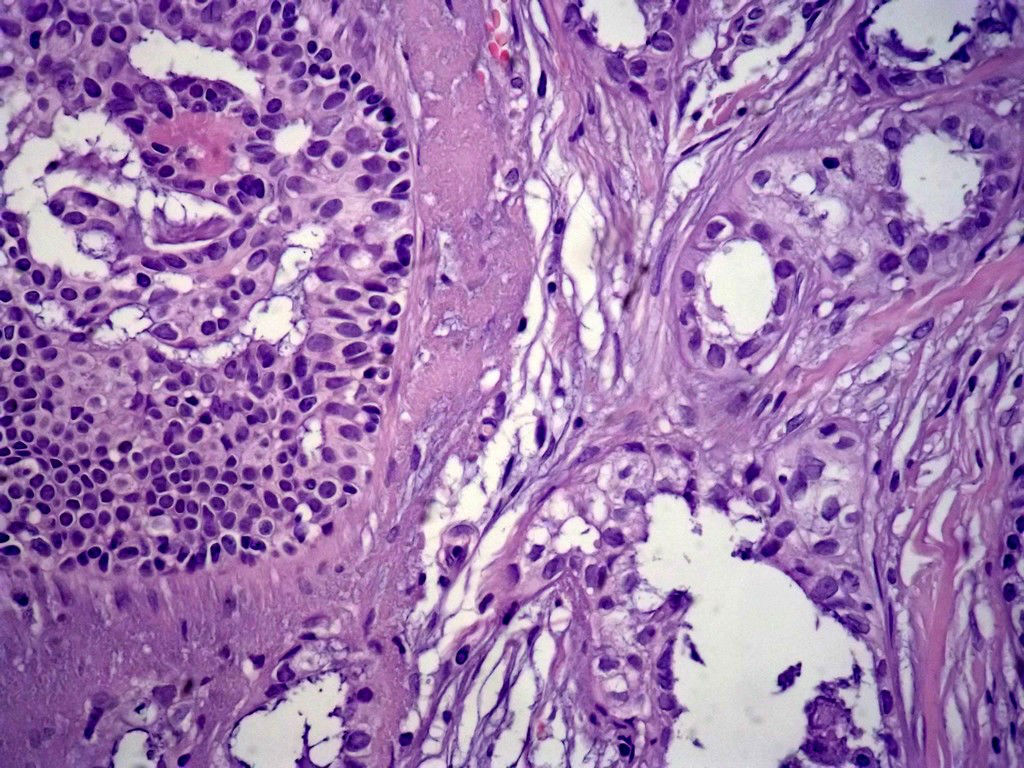

今天的一例术中冰冻。女,49岁,乳腺肿块。人气不旺,换个标题

腺病?癌?其他?(12楼常规,24楼免疫组化及会诊结果)图1

标签:浸润性导管癌 分泌癌 硬化性腺病

乳腺分泌型癌

导管是乎可见双层上皮,部分上皮增生并有一定异型,考虑硬化性腺病,待石蜡。

导管可见双层上皮,部分上皮增生并有一定异型,考虑硬化性腺病

腺体与腺体之间的对比差异太大,不放心,不除外是癌,如果是我的病例,再次取材冰冻

占楼传常规1-11为冰对。

浸润性导管癌。冰冻切片的诊断是很困难,直接诊断癌风险很大,但是在明显正常的导管间这种成片、成巢有腔的细胞团块也不是良性的表现,有的还似乎有围绕正常导管生长的倾向。诊断ADH还可以,但是不能归到任何一种DCIS的生长方式里。这例值得我好好学习。